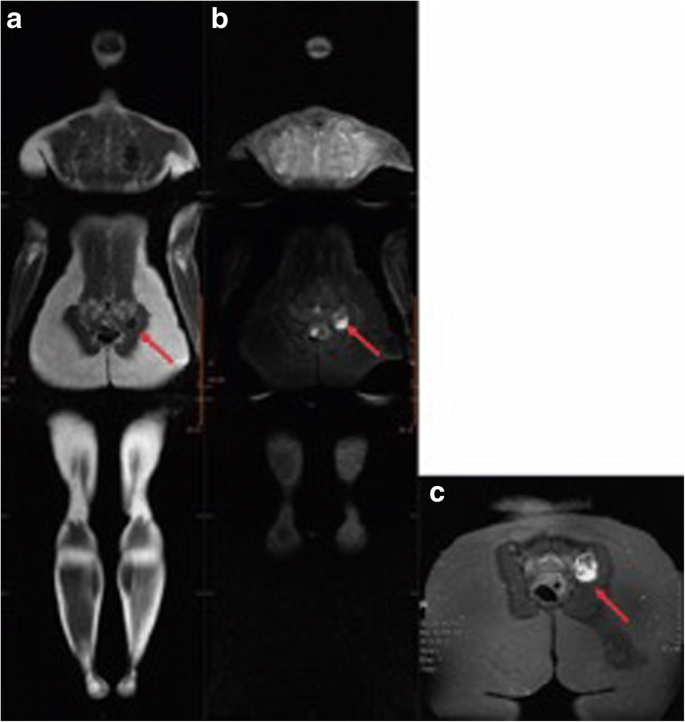

Whole Body Magnetic Resonance Imaging Of Li Fraumeni Syndrome Patients Observations From A Two Rounds Screening Of Brazilian Patients Cancer Imaging Full Text

Li Fraumeni Syndrome Body Mri